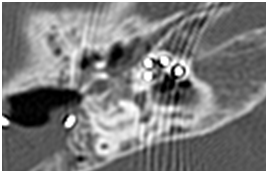

Cases of electrode misplacement into the hypotympanum (Figure 3)

This 2 patents has a rotate cochlea. We extended posterior tympanotomy, extracted an electrode from hypotympanic cells without damage andreinserted correctly the same electrode array via round window.

Figure 3 Axial CT left temporal bone demonstrated the case of insertion of the electrode into the hypothympanum cells.